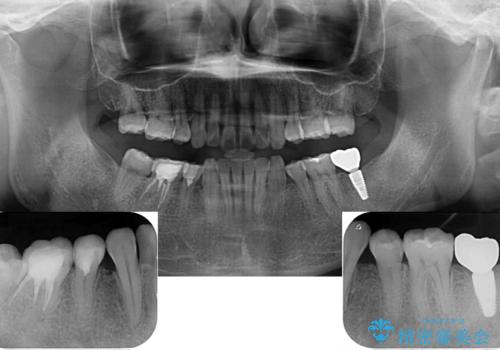

左下の欠損部は、世界中で高い信頼を得ているストローマンインプラントを用いて治療を行うこととしました。

ただし、長期間欠損を放置していたことで、咬み合う上の奥歯が動いてしまっていたので、まずは上顎奥歯の部分矯正を行い、より理想的な咬み合わせを目指すこととしました。

まず生活歯髄療法を行い、その後部分矯正やインプラント処置を行いましたが、最初の処置から1年以上経っても右下奥の処置歯の神経組織に異常は認められませんでした。

部分矯正を行ったことで、違和感のない咬み合わせを達成することができました。